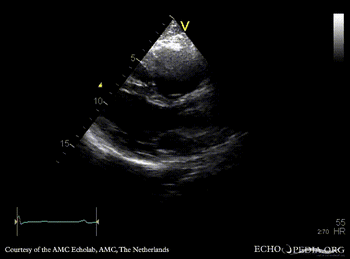

ARVD

Courtesy of: AMC Echolab, AMC, The Netherlands

A4CH: dilated right ventricle, reduced systolic function